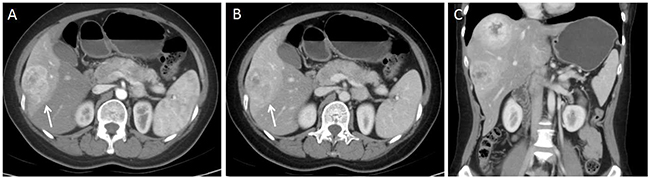

Figure 3: 40-year-old woman with G2 pancreas NET. (A) Axial CT image in the hepatic arterial phase shows a hyper enhanced liver metastasis in the right lobe of liver(arrow). (B) On portal venous phase, the lesion demonstrates washout enhancement pattern(arrow). (C) No regional or distal lymphadenopathy is present on coronal portal venous phase CT image.